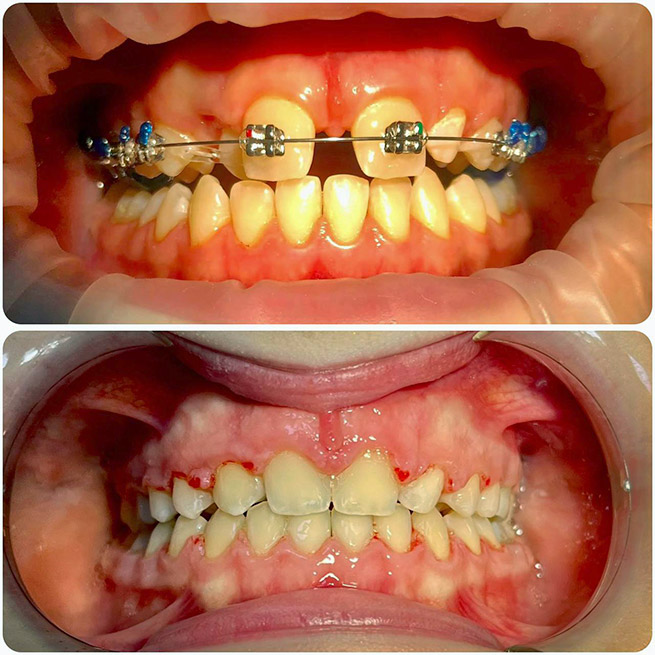

Брекет-системи – класичне та ефективне рішення для виправлення прикусу та вирівнювання зубів. Я працюю з:

- Металевими брекетами (надійні та доступні);

- Самолігуючими брекетами (металеві та керамічні);